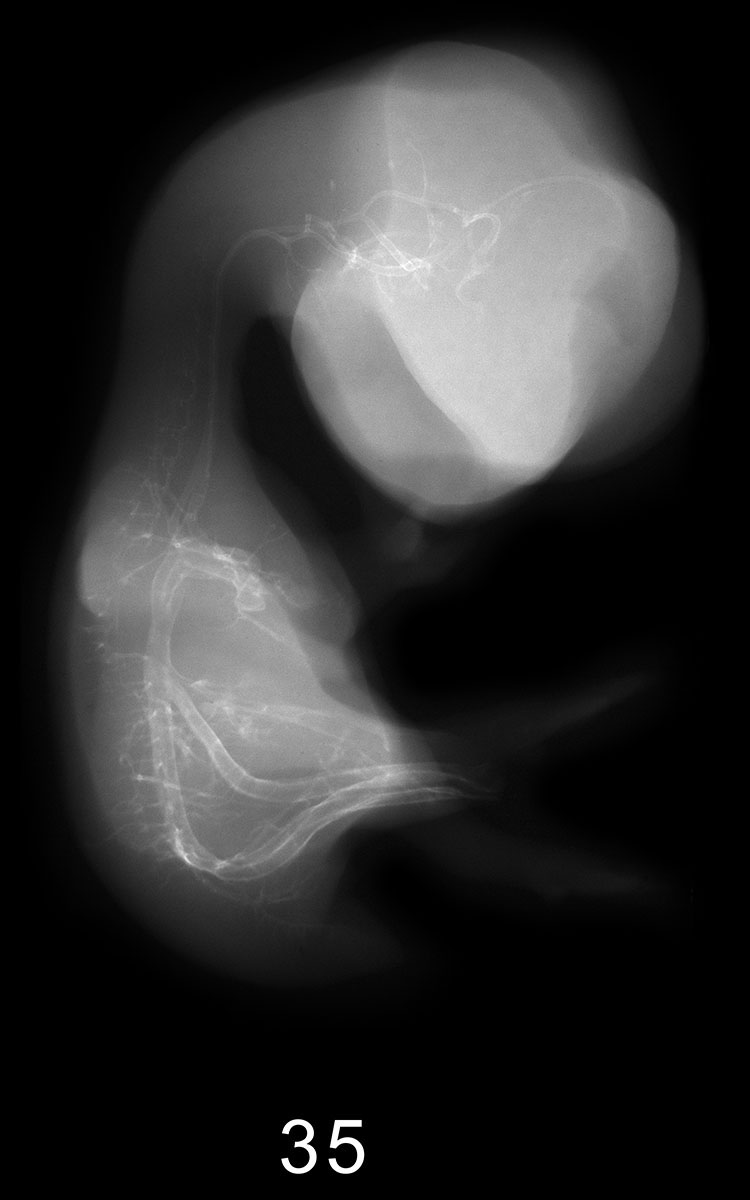

Chick Embryo Microangiography

Images listed by Hamburger-Hamilton (HH) Stage

Hamburger-Hamilton (HH) stages are a system used by those who study chick embryo development to describe the apparent maturity of the developing chick from laying of the egg to hatching. An embryo is assigned an HH stage (numbered from 1 to 46) based on its physical shape and visible features (morphology). This staging system is not dependent on the chronological age nor the size of the embryo, which are susceptible to variations due to breed, temperature during incubation, season, and time between egg laying and incubation. The stages, are in a sense, arbitrary levels of maturity based on multiple physical features. For example, embryos that might have different ages or sizes might be assigned the same HH stage based on their external appearance due to the natural variation which occurs between individuals or due to differing conditions during incubation.